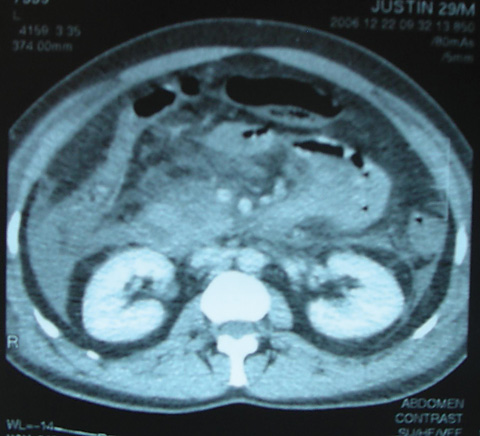

Bilateral renal halo sign in acute pancreatitis

Med J Aust 2008; 189 (4): 228. || doi: 10.5694/j.1326-5377.2008.tb01991.x